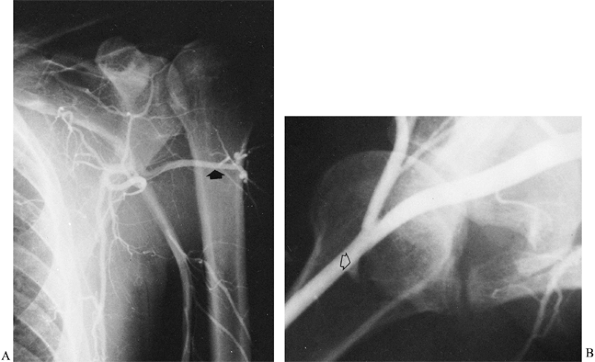

This invasive procedure should be performed to document this syndrome

abduction and external rotation (Fig. 59.6).

Follow the dye distally to visualize the posterior humeral circumflex

artery. In a positive arteriogram, the posterior humeral circumflex

artery is patent with the arm at the side and occludes with the arm in

external rotation and abduction. In normal extremities, the posterior

humeral artery does not occlude in this position.

Figure 59.6. Subclavian arteriogram of a patient with quadrilateral space syndrome. A: With the arm at the side, the posterior humeral circumflex artery is patent (arrow). B: With the arm in abduction and external rotation, occlusion of the posterior humeral circumflex artery is seen near its origin (arrow).